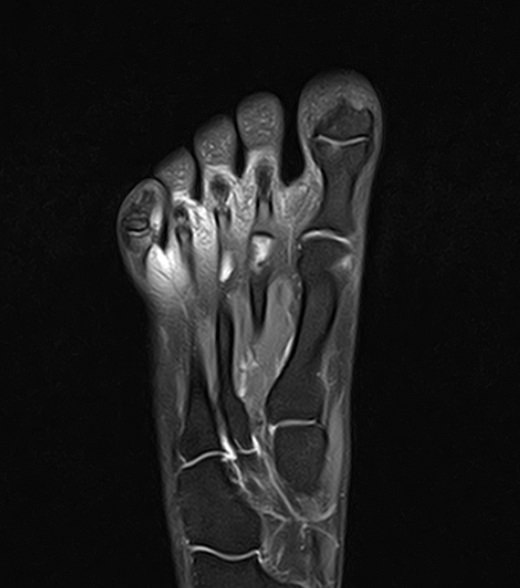

В клинике «Доступная медицина» данное исследование проводится на современном высокопольном магнитно-резонансном томографе экспертного класса TOSHIBA VANTAGE TITAN 1,5 Тесла. Напряженность магнитного поля 1,5 Тесла обеспечивает высокую разрешающую способность аппарата, что позволяет выявлять минимальные изменения в тканях и диагностировать заболевания на начальной стадии.

В большинстве случаев проводится стандартная магнитно-резонансная томография стопы без использования контраста, однако в некоторых случаях требуется контрастное усиление для детализации патологических очагов. Для этого применяется контрастное вещество на основе гадолиния (элемент, относящийся к редкоземельным металлам), которое полностью выводится из организма в течение суток преимущественно почками.